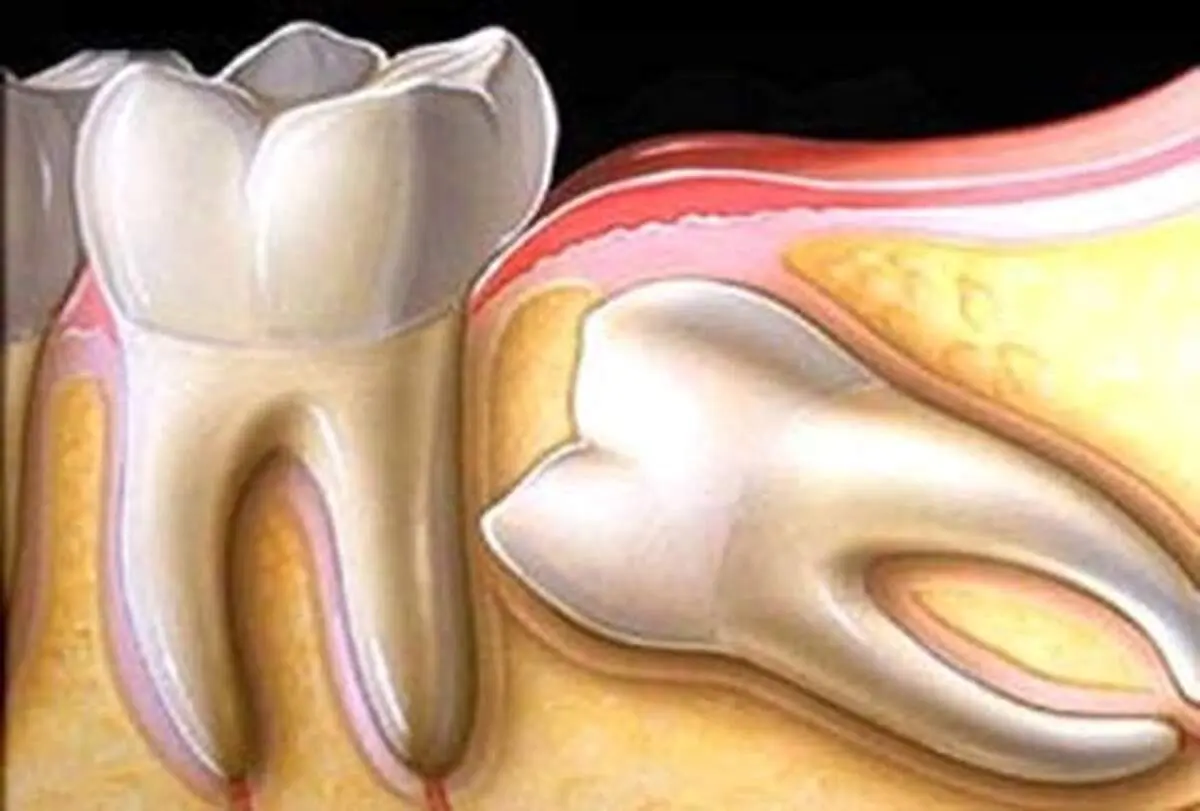

در ساخت این خمیر دندان از اجزای اصلی و طبیعی مواد سازنده دندان کمک گرفته شده است. برای ساخت آن از هیدروکسی آپاتیت یا همان کلسیم کریستالی استفاده شده است و به محض آنکه به دندانها اعمال میشود مادهای را بر سطح دندان منتشر میکند که بعد از 3 دقیقه به ساختار طبیعی مینای دندان میچسبد و شیارها و حفرهها را پر میکند.